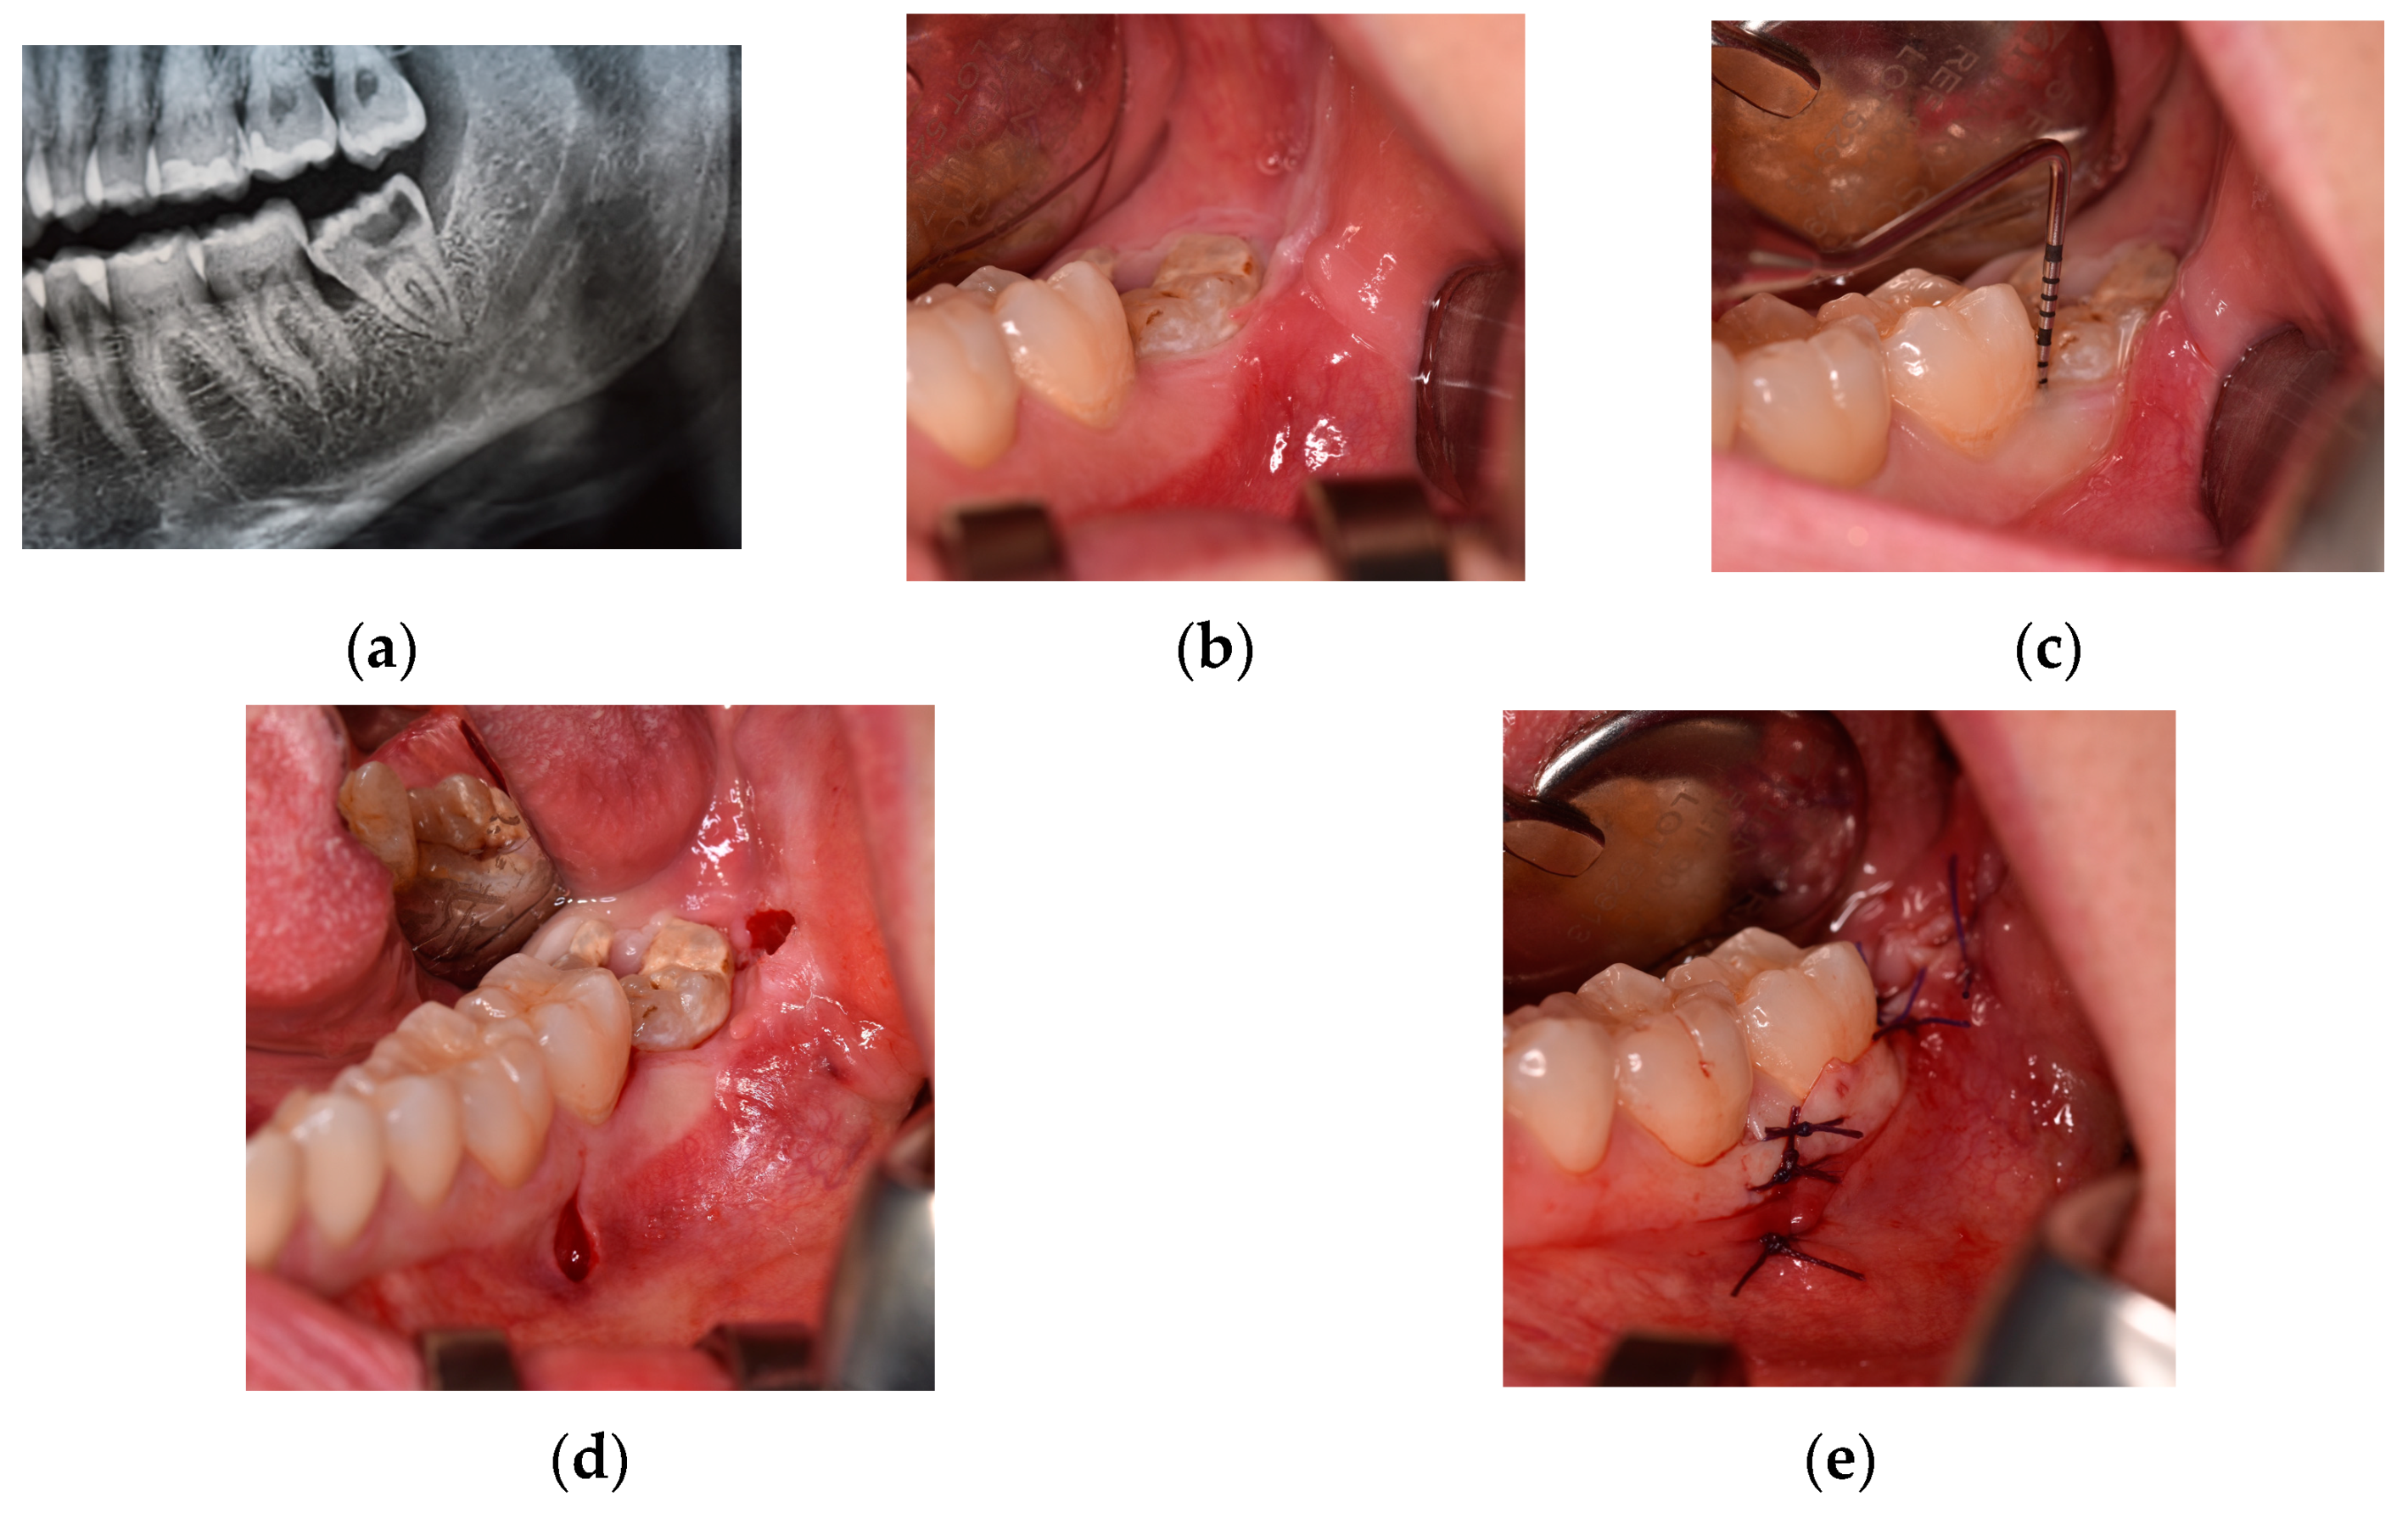

Figure 2. Trapezoidal flap (class IB position): (a) pre-operative detail of panoramic radiograph; (b) pre-operative clinical evaluation; (c) pre-operative periodontal probing of pocket at distal site of the second molar; (d) intra-operative mesial- and distal-releasing incisions; and (e) final wound closure.

As shown in Figure 2, the TRAP technique [22] provides an intrasulcular-buccal incision at the level of adherent gingiva. It begins at the level of the first molar, then continues at the level of second molar, and then ends with a releasing incision directed towards the distal-buccal side of the second molar, as in DETP. Furthermore, this flap involves a second mesial-releasing incision, which begins at the distal-buccal gingival margin of the first molar, to allow for simpler flap dissection.